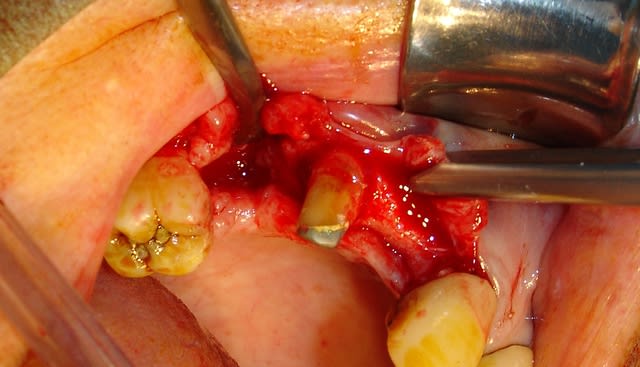

l'interactive, (t'ain qu'il est beau!!!)

mise en place au CA qui bloque à 45Ncm...on est à 1 ou 2 mm de la crête....pas de problème, on retire le Fm (sympa, la vis, car il y a un filetage dans le Fm, ne risque plus de tomber!!!) et on se reprend direct dans le col de l'implant à la clef à cliquet...comme d'hab quoi...;-)